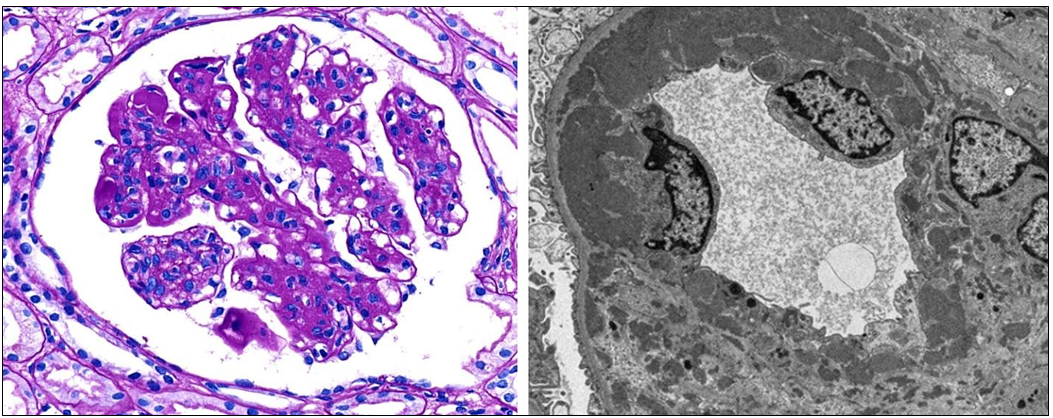

31세 여자가 단백뇨와 혈뇨가 있어 신장조직검사를 하였다. 피부의 광과민성과 반복되는 구강궤양이 있었다. 혈액검사에서 백혈구감소증을 보이며 혈청검사에서 항DNA 항체와 항Sm 항체의 증가가 발견된다. 신장조직검사 소견이다. 이 병의 발생기전은?

[전신홍반루푸스, Systematic Lupus Erythematosus (SLE)]

• 전신홍반루푸스는 자가면역항체 및 면역복합체가 전신을 침범하는 자가면역질환이다.

• 이때 가장 심각한 합병증 중 하나는 루푸스콩팥염 (lupus nephritis)로, 혈액에 떠돌던 면역복합체가 신장에 침착해 사구체 기저막 손상과 염증반응을 유발하면서 나타난다.

• 따라서 발생기전은 5번, 제3형 과민반응인 면역복합체매게 과민반응이다.